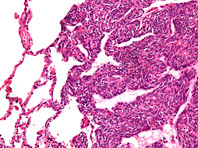

Онкологи из США установили: воздействие на белок BRD9 (бромдоменсодержащий белок 9) способно блокировать развитие синовиальной саркомы — опухоли, возникающей из синовиальной оболочки суставов, сухожильных влагалищ и фасций верхних и нижних конечностей. Чаще всего поражает нижние и верхние конечности в области крупных суставов; редко — область шеи или груди, передает «Российская газета». Что важно, в начале…